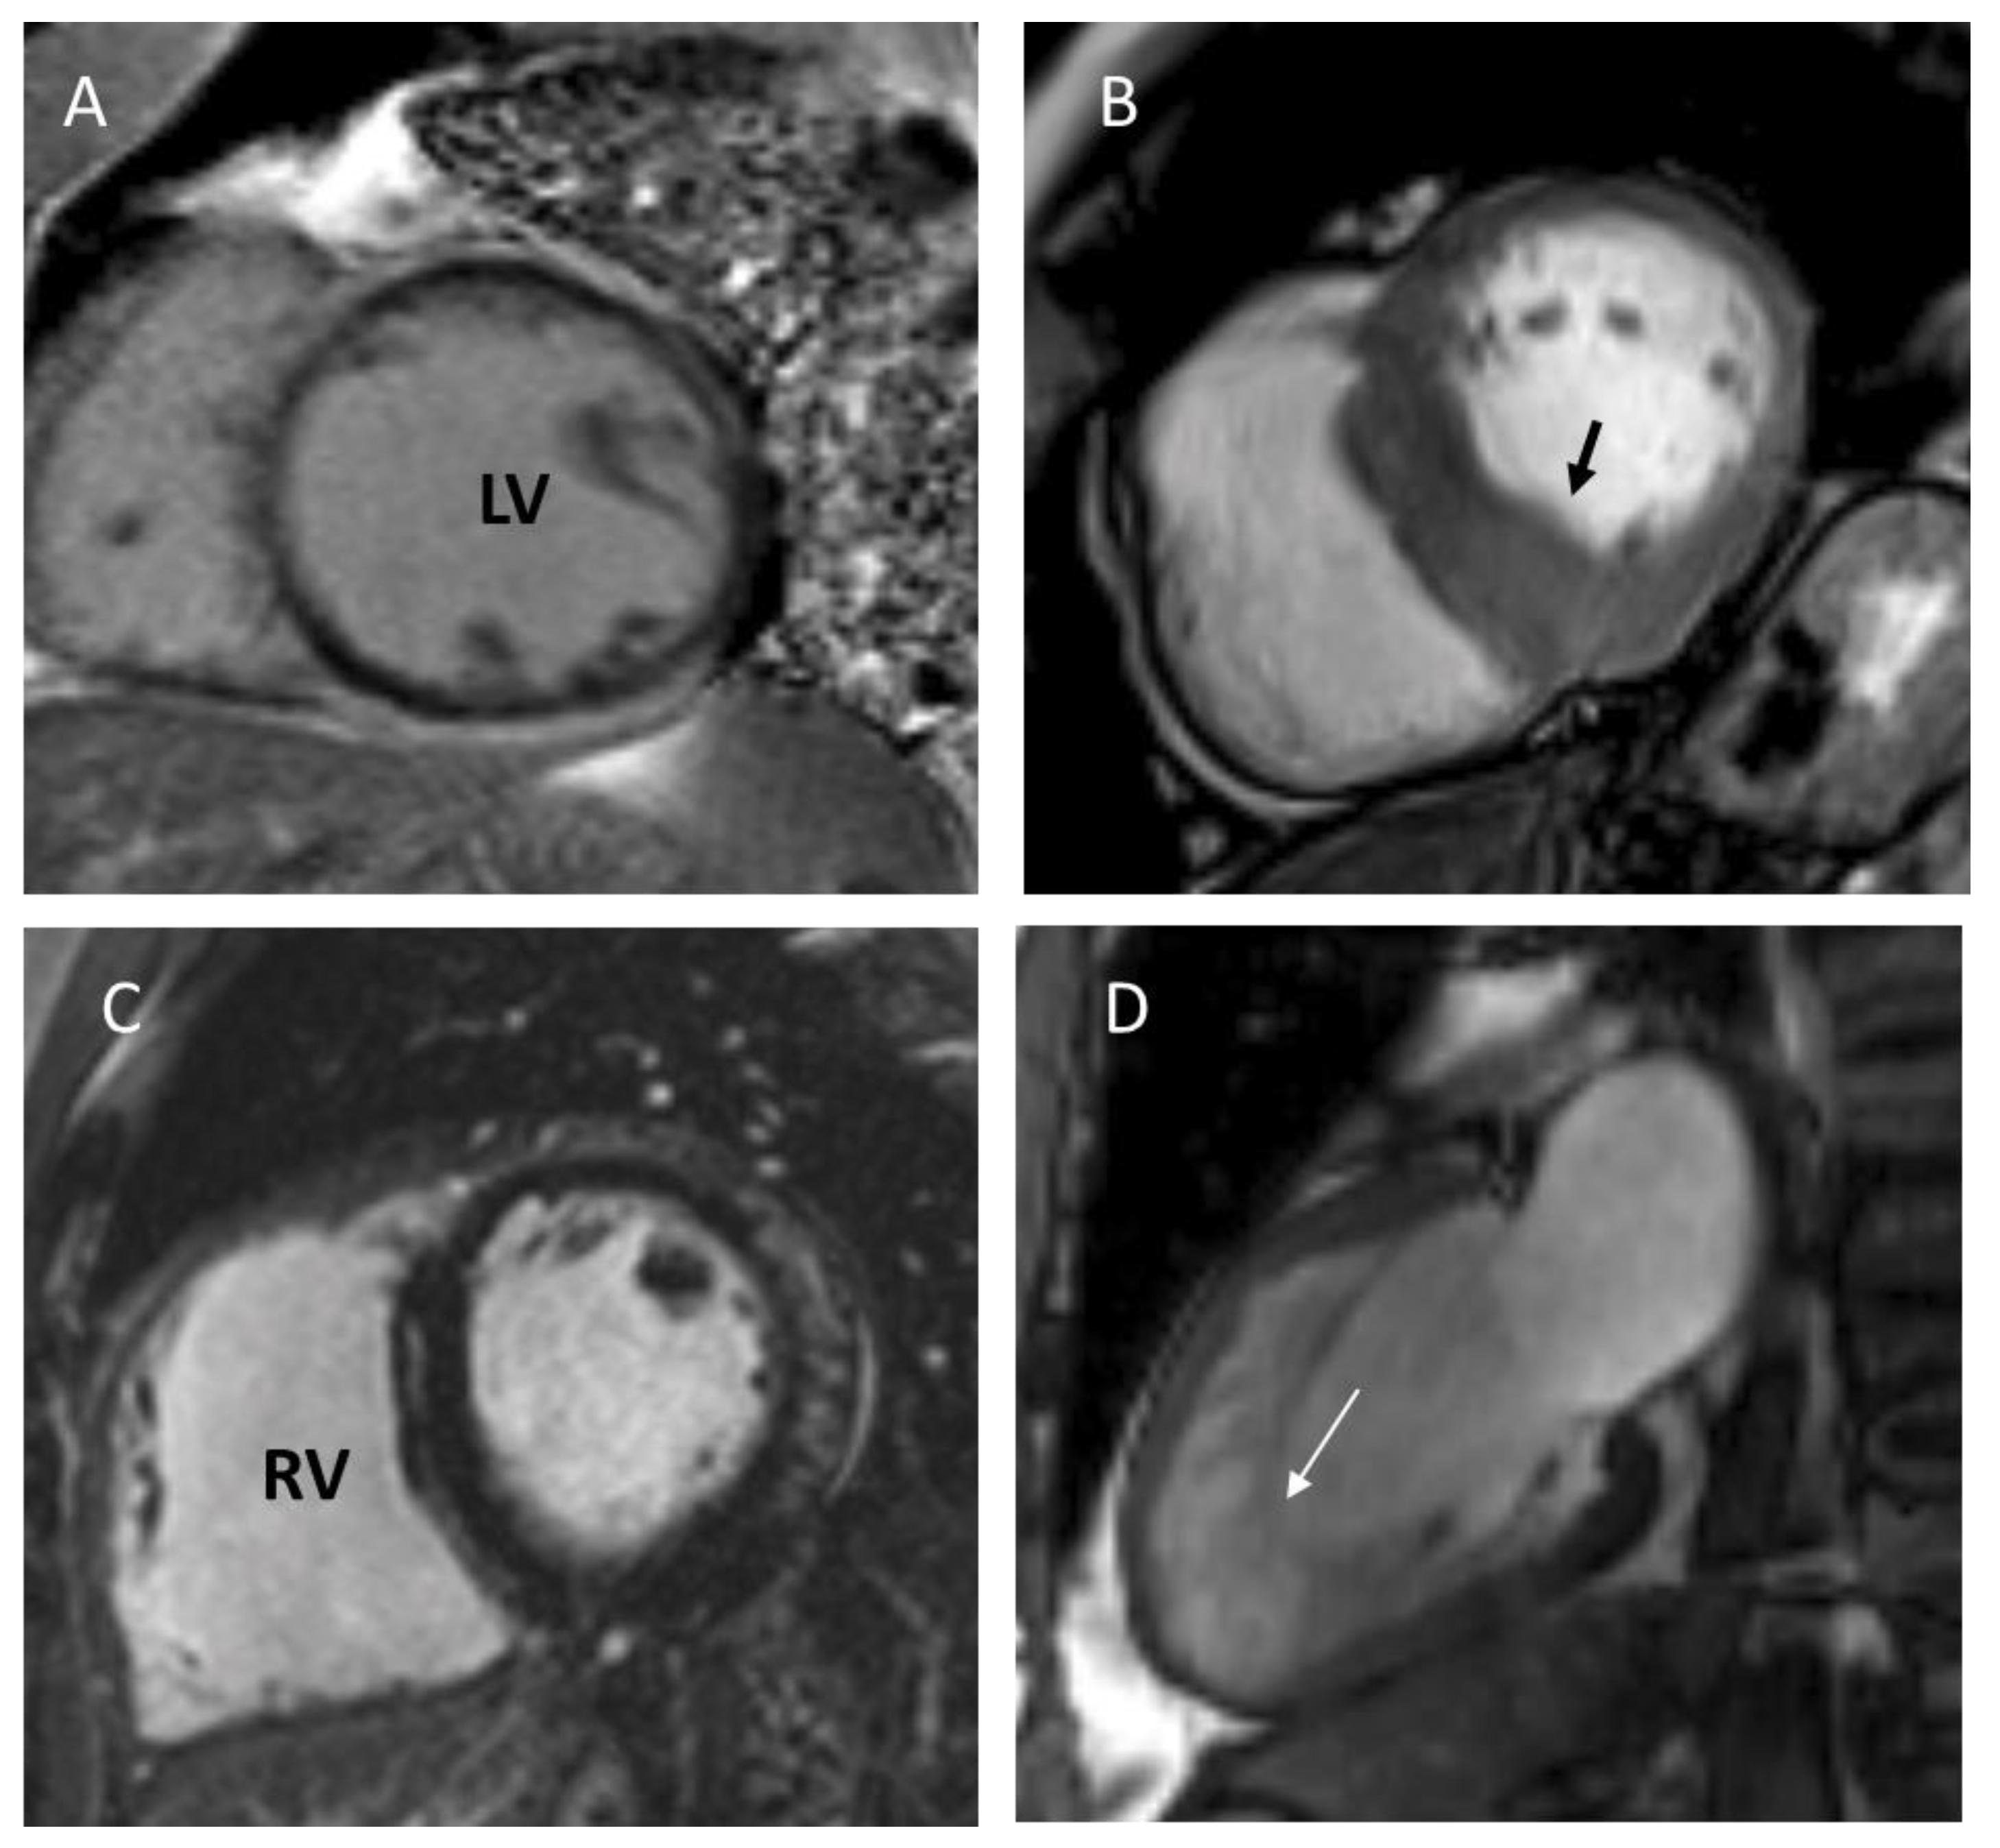

6. Left Ventricular Noncompaction

6.3. Diagnosis and Disease Mechanism